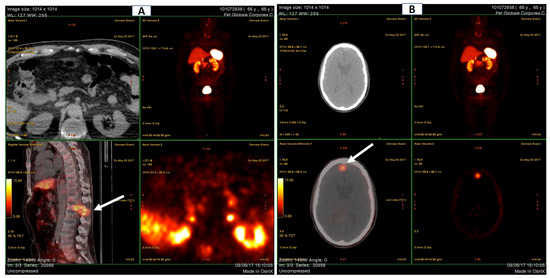

Bone mass evaluation by dual energy X-ray absorptiometry (DEXA), reported in Figure 3, showed severe osteoporosis of both femurs (T-score −5.0 and −5.4 SD for left and right, respectively) and the lumbar spine (T-score −4.5 SD).

Although the DEXA cannot be considered a radiological examination/imaging diagnostic tool, the left femoral neck appeared much shorter, compatible with a closed fracture. Moreover, and more interestingly, at the T12/L1 spine level, an hyperdense area was clearly detectable. This was further investigated by the mean of Global PET Ga68, that showed hypercaptation at the expansive formation in T12-L1 with narrowing of the vertebral canal and bone lysis at the L1 vertebral body and transverse and spinous processes levels. Moreover, the exam denoted an increased uptake in a small encephalic area of the frontal cortex (Figure 4A,B).

Figure 3. Bone mass evaluation by DEXA. The hips are shown at the right of the figure (left hip, L, above; right hip, R, below), the spine is on the left. The bone densitometry values (shown in the DXA results summary table) are far below the osteoporotic threshold (T-score < −2.5 SD). The inferior panels report the patient’s bone mineral density (BMD) levels compared to those expected at the same site for age-matched subjects: normal values above the grey band (osteopenic) and frankly osteoporotic below the black band (osteoporotic). The different length of the right and left femoral necks, indicated by the red arrows, may indicate a closed fracture. The hyperdense area at T12-L1 is indicated by a yellow arrow.